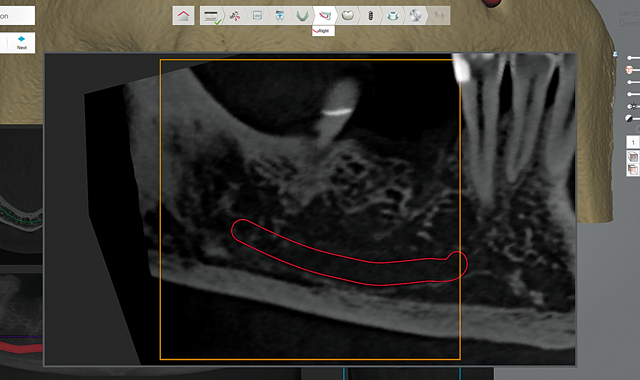

Fig. 2 Mandibular nerve

When treating the posterior mandible, one of the initial steps includes identifying and marking the mandibular nerve canal and mental foramen (Fig. 2).